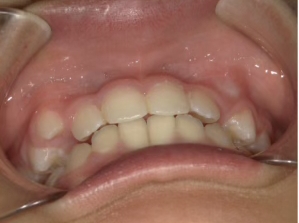

治療中⑨ 中3:14y4m

モノブロック装置で左上八重歯が改善しました

今後、必要によりマルチブラケット法へ移行予定です